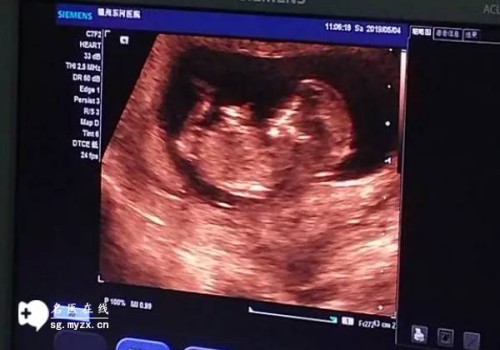

隨著試管嬰兒技術(shù)的發(fā)展,越來越多的高齡女性希望通過試管嬰兒來實現(xiàn)自己的母親夢。然而,由于子宮腺肌癥的存在,許多高齡女性發(fā)現(xiàn)自己有可能無法通過試管嬰兒來實現(xiàn)這一夢想。為了更好地了解試管嬰兒的成功率,我們對有子宮腺肌癥的高齡女性進行了一項調(diào)查。

• 高齡女性是指年齡超過37歲的女性。子宮腺肌癥是指子宮內(nèi)膜存在異常增生,可導(dǎo)致無痛性子宮出血。該病一般分為容易、中度和重度3種類型,其中重度子宮腺肌癥的發(fā)病率較高。

• 該調(diào)查的范圍為國內(nèi)某三甲醫(yī)院的試管嬰兒患者,共有100例患者,其中50例為有子宮腺肌癥的高齡女性,另外50例為沒有子宮腺肌癥的高齡女性。結(jié)果發(fā)現(xiàn),有子宮腺肌癥的高齡女性試管嬰兒成功率為42%,而沒有子宮腺肌癥的高齡女性試管嬰兒成功率為54%,可見有子宮腺肌

癥的高齡女性試管嬰兒成功率略低于沒有子宮腺肌癥的高齡女性。

• 由此可見子宮腺肌癥的存在會影響高齡女性的試管嬰兒成功率,但不會影響其他年齡段的試管嬰兒成功率,因此高齡女性在嘗試試管嬰兒之前,應(yīng)該提前進行子宮組織學(xué)檢查,以排除子宮腺肌癥的可能性,以便提高試管嬰兒的成功率。此外建議高齡女性在試管嬰兒之前進行全面的健康檢查,改善生活方式,提高身體素質(zhì),以提高試管嬰兒的成功率。

盡管高齡女性有子宮腺肌癥的試管嬰兒成功率略低于沒有子宮腺肌癥的高齡女性,但并不意味著高齡女性完全無法通過試管嬰兒來實現(xiàn)自己的母親夢,只要在試管嬰兒前提前進行全面的健康檢查,改善生活方式,提高身體素質(zhì),高齡女性也有可能通過試管嬰兒來實現(xiàn)自己的母親夢。